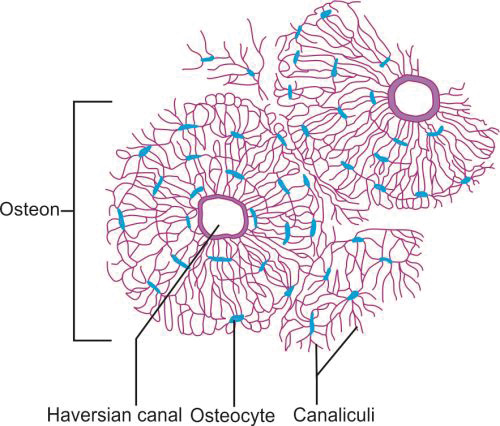

Microscopic Structure of Cortical Bones (Fig. 1.14)

Cortical bone consists of a number of columns of cells called “osteon”. Each osteon has layers of bone cells like osteoblasts, osteocytes and osteoclasts around a central canal called “Haversian canal”. The outer border of an osteon is lined by a cement line which is a region of collagen-poor bone matrix.

The Haversian canal surrounds the blood vessels and nerves cells throughout the bone and communicates with the osteocytes in the lacunae through canaliculi.

“Volkmann's canals” run perpendicular to the “Haversian canals”. They interconnect the Haversian canal with each other and the periosteum. These canals allow for the transfer of nutrients.